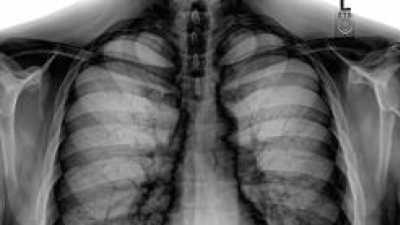

În prezent, în România, puţine sunt cazurile în care medicii ţin cont de numărul iradierilor la care a fost expus un pacient, astfel încât se ajunge, uneori, ca pentru o simplă fractură să se repete de mai multe ori o radiografie. De asemenea, există persoane care solicită realizarea unor investigaţii iradiante cum sunt radiografiile sau tomografiile computerizate pe baza unor presupuneri personale, fără recomandarea unui specialist.

Astfel, efectuarea la întâmplare a unor astfel de investigaţii iradiante este periculoasă, deoarece fiecare radiografie şi fiecare tomografie computerizată determină modificări ireversibile în corp. Astfel, cu cât facem mai multe analize iradiante, cu atât modificările din organism sunt mai importante.

Aceste tipuri de investigaţii sunt cu adevărat necesare atunci când nicio altă analiză nu poate oferi informaţiile necesare cu privire la starea de sănătate a pacientului.